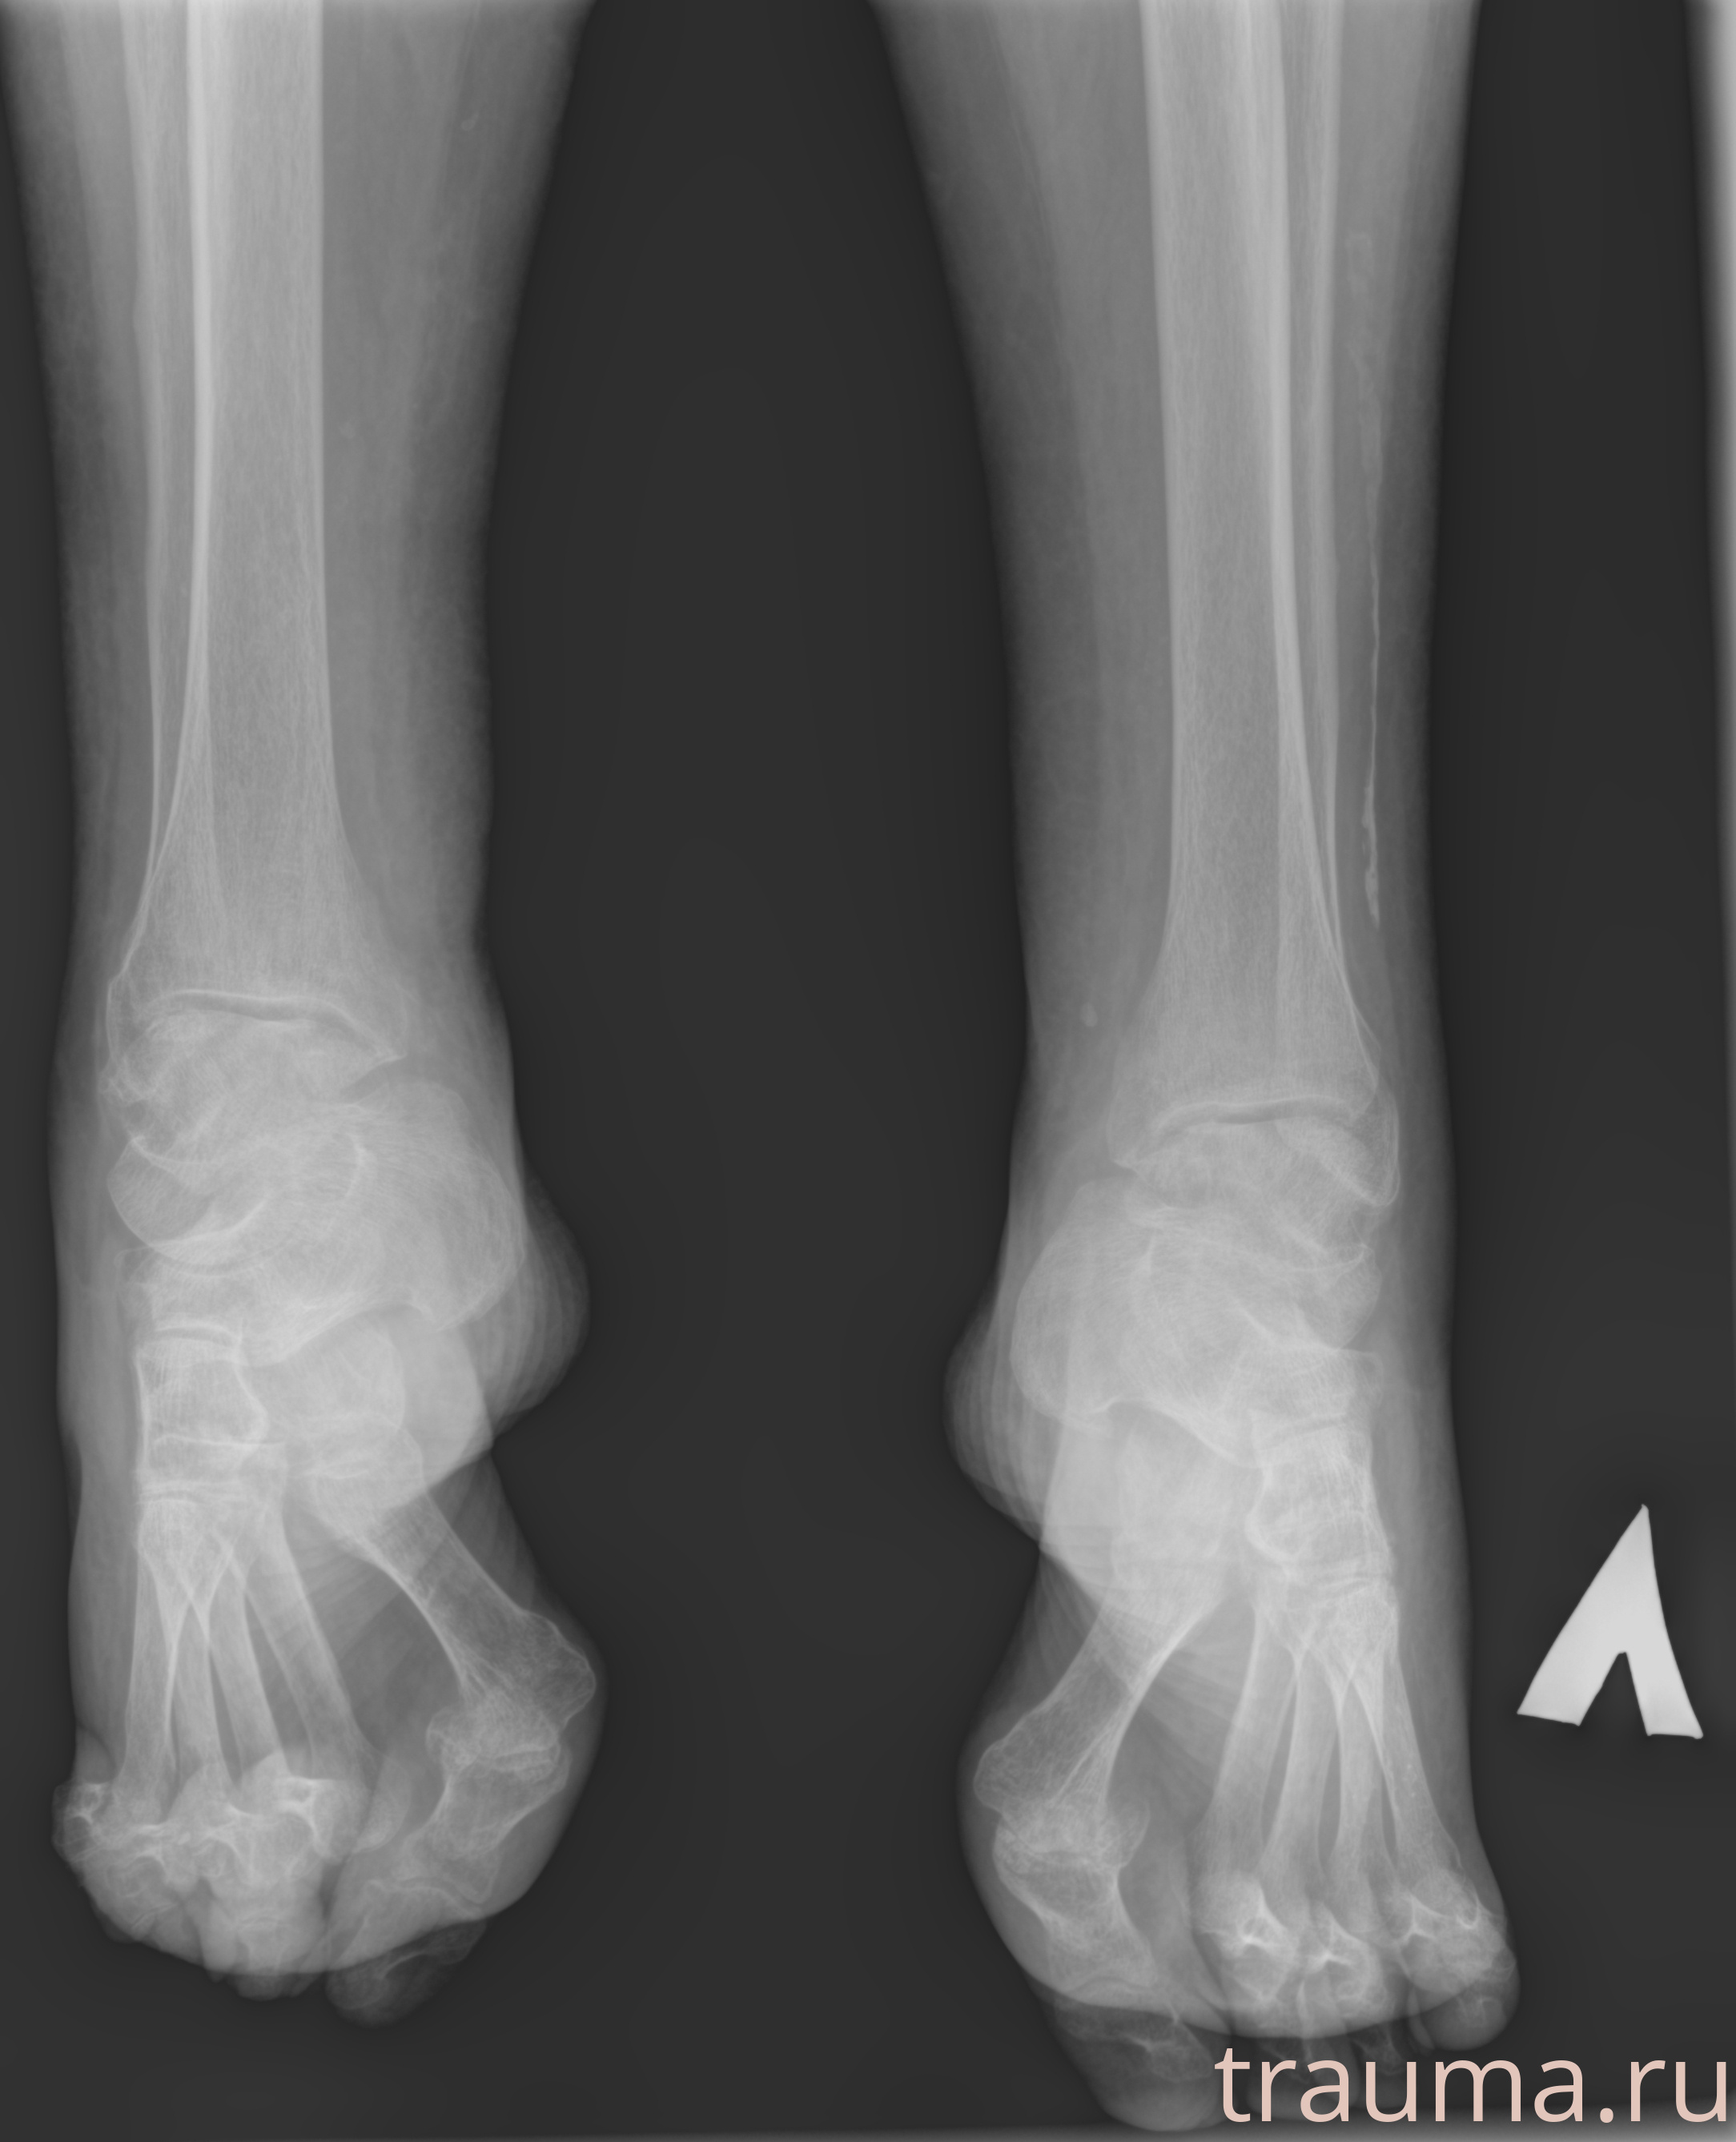

Рентгенограммы

Рентген на дому: по вашему адресу приезжает врач-рентгенолог, травматолог-ортопед с мобильным рентгеновским аппаратом, проводит диагностику травмы или заболевания, делает необходимые рентгенограммы, дает рекомендации по дальнейшему лечению. Получить качественные снимки в домашних условиях возможно благодаря уникальной методике, разработанной МосРентген Центром для института  Склифосовского